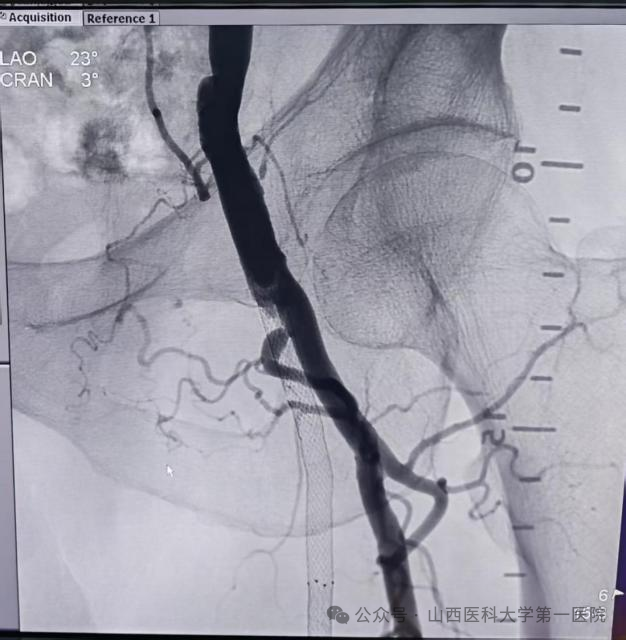

旋切术中动脉造影:左侧股浅动脉显影

面对这一棘手病例,血管外科王贵明主任团队结合丰富的临床经验与国际前沿技术,制定出个体化、精准化治疗方案,采用先进的JETSTREAM外周血管斑块旋切导管系统实施微创介入治疗。术中在血管透视引导下,精准识别病变部位,通过导管高速旋转头端对支架内斑块及增生内膜进行粉碎,并依靠系统内置的螺旋输送装置将碎屑有效导出体外,术中同时发现支架远端为继发血栓形成,决定使用Rotarex机械血栓切除系统将远端血栓消除,并结合导丝头端通过病变的形态改变及触觉反馈,考虑支架内病变主要是内膜增生相关,决定使用药物球囊扩张技术,抑制内膜增生。此次手术彻底贯彻“leave nothing behind”治疗理念,相较传统导管溶栓或再次支架植入等治疗方式,在微创性、远期疗效及安全性方面均展现出显著优势。